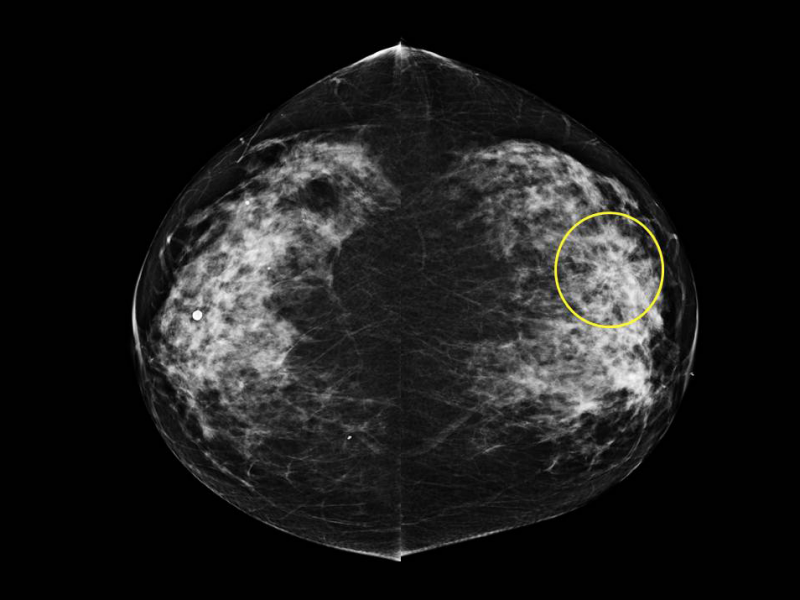

Patient 1: Bilateral MLO views from screening mammography in a 53-year-old woman.